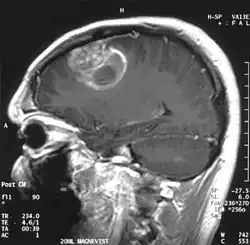

| Glioblastoma observado em ressonância magnética | |

Quando visto através da ressonância magnética, os glioblastomas frequentemente aparecem como lesões com realce em anel. No entanto, esta aparência não é específica, já que outras lesões como abscessos, metástases e esclerose múltipla tumefativa podem ter uma aparência similar.[12]

O diagnóstico definitivo do glioblastoma multiforme requer uma biópsia estereotática ou uma craniotomia com ressecção do tumor e confirmação patológica.